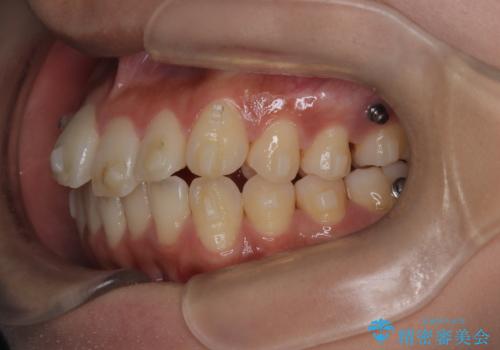

前歯の叢生・Ⅱ級咬合を改善|TADを用いた遠心移動+インビザライン矯正

- 前歯のガタガタと臼歯関係のⅡ級(上顎の歯列が前方にある状態)を改善するため、TAD(歯科矯正用アンカースクリュー)を使用したインビザライン矯正を計画しました。まずTADを上顎の適切な位置に設置し、それを固定源にして奥歯を後方(遠心)へ移動させ、十分なスペースを確保します。その後、インビザラインによるマウスピース矯正で前歯の歯列を整え、臼歯関係を正常化します。治療期間はおよそ1年半〜2年を想定しています。

前歯部の叢生(ガタガタ)と臼歯関係のズレを改善するため、抜歯をせずに奥歯を後方へ移動(遠心移動)させることを選択しました。TADという小型のアンカースクリューを顎骨に設置することで、確実かつ効率的に奥歯を後方へ移動させました。併せて透明で目立ちにくいインビザラインを用いることで、審美性を保ちながら治療を進めることが可能でした。患者様の負担が少ないマウスピース矯正と固定源のTADを組み合わせることで、抜歯することなく歯並びと噛み合わせを大幅に改善でき、大変ご満足いただけました。